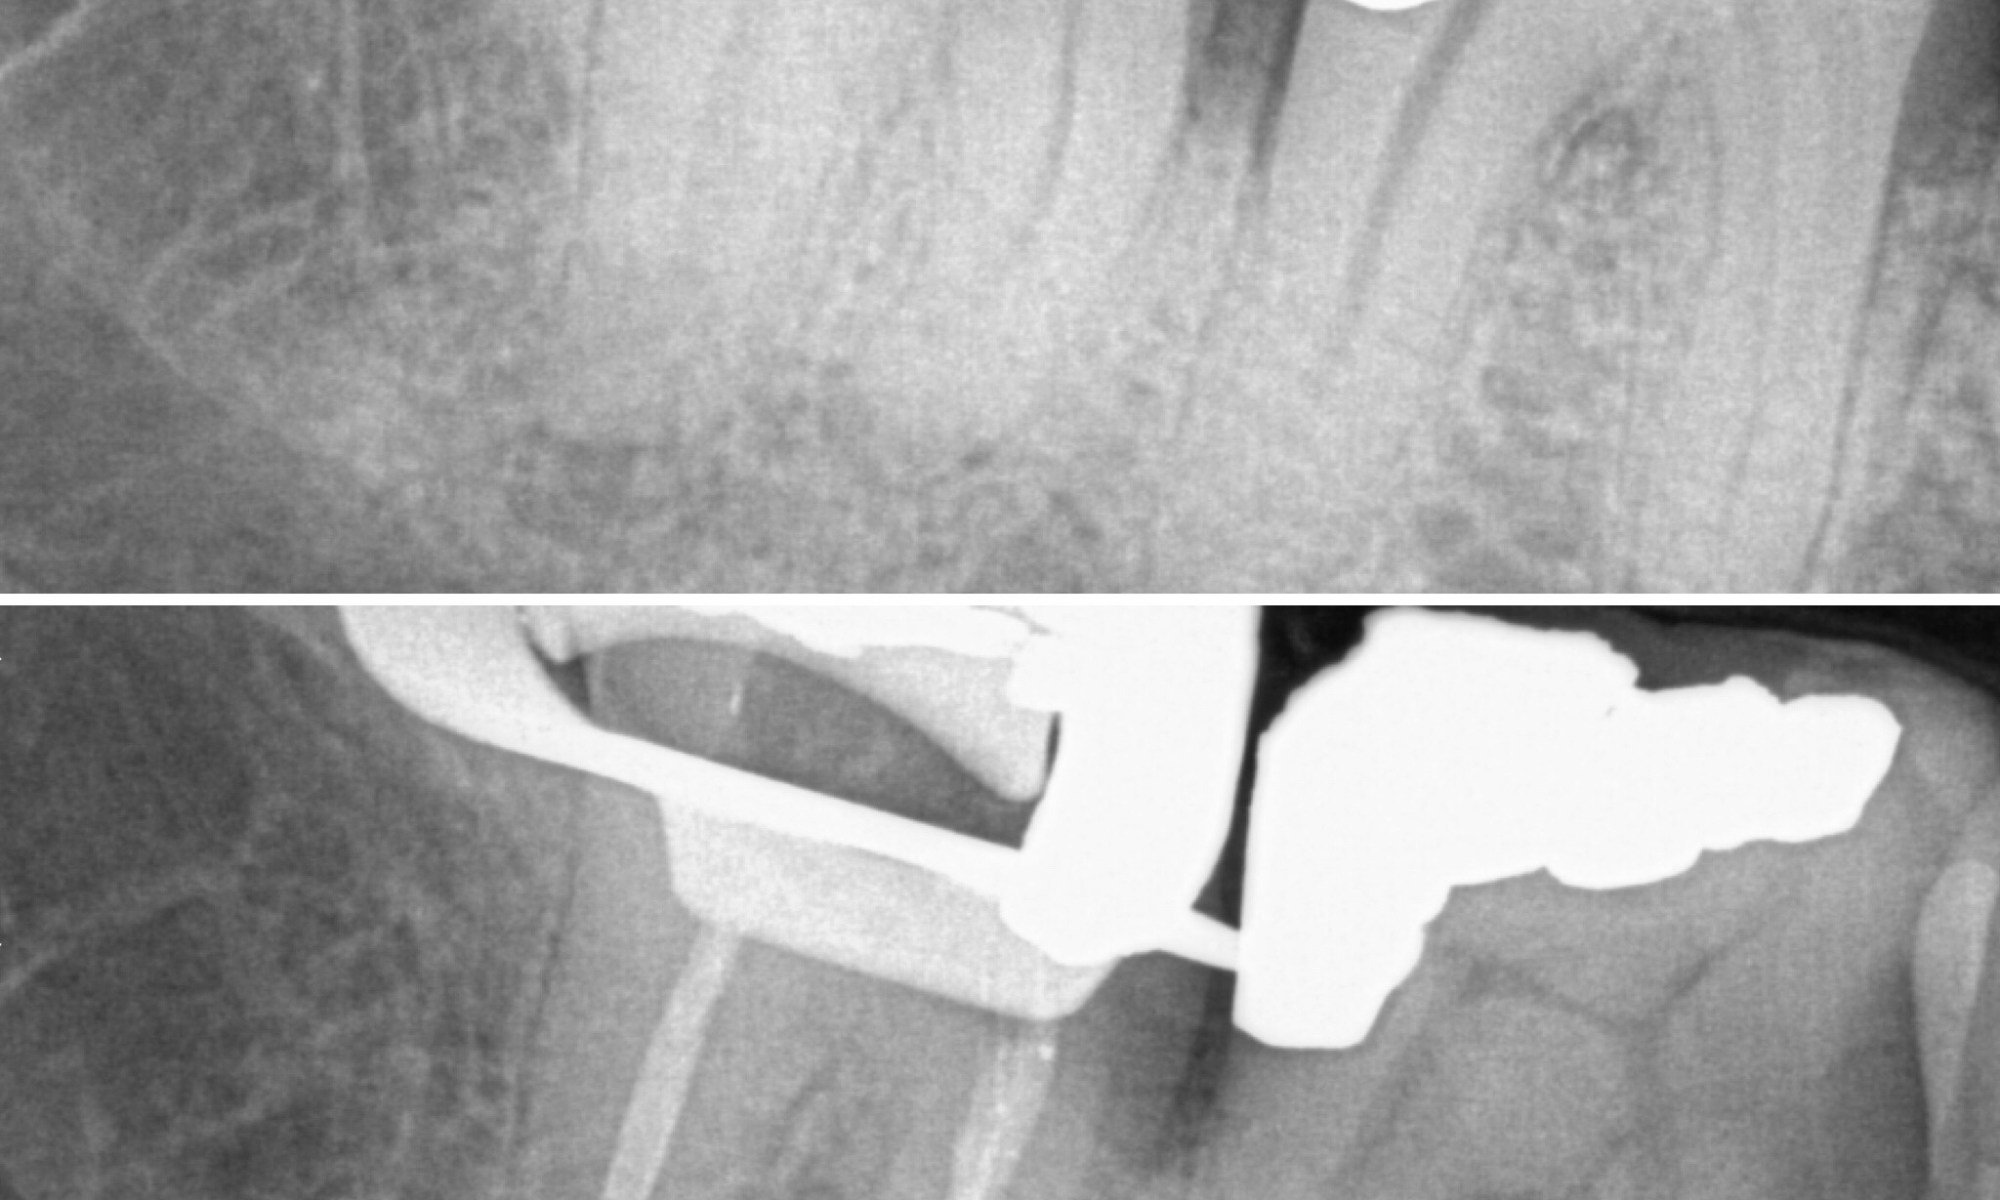

Had the great privilege to treat my senior dentist. Dentists also require treatment and regular hygiene! Related